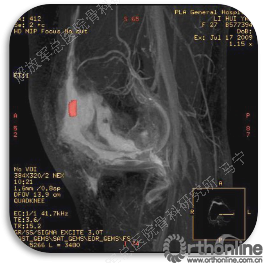

首先经过核磁的检查、评估,初步确定软骨损伤范围,利用T2maping检测序列对软骨的信号区分。图中我们可以看到软骨损伤的范围,并通过计算机计算出大概的面积。